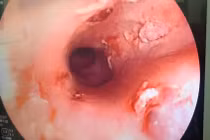

Chiếc xương cá dài 3cm, nhiều sắc cạnh cắm sâu trong thực quản người bệnh đã được nội soi gắp thành công. Hóc xương cá gây nhiều biến chứng nguy hiểm nên cần biết cách phòng tránh.

(khoahocdoisong.vn) - Các bác sĩ Bệnh viện nhi đồng Đồng Nai đã rất bất ngờ và ngạc nhiên không hiểu sao một bệnh nhi lại có thể nuốt miếng xương cá hình dạng phức tạp, giống chân vịt vào đến thực quản.